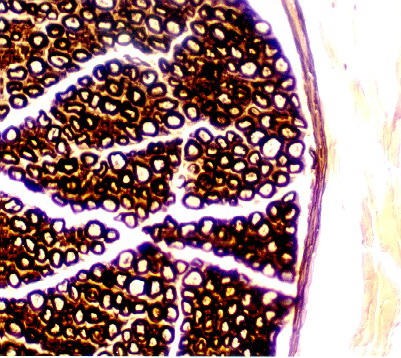

The following is a section through a peripheral nerve stained with Osmium tetroxide to bring out the myelin.

The myelin sheath is stained because of the abundance of lipids in the membranes wrapping around the axon. Each myelinated axon looks like a donut. You can also see adipose cells well in this section. They contain stained, preserved fat droplets that stain dark brown-black.